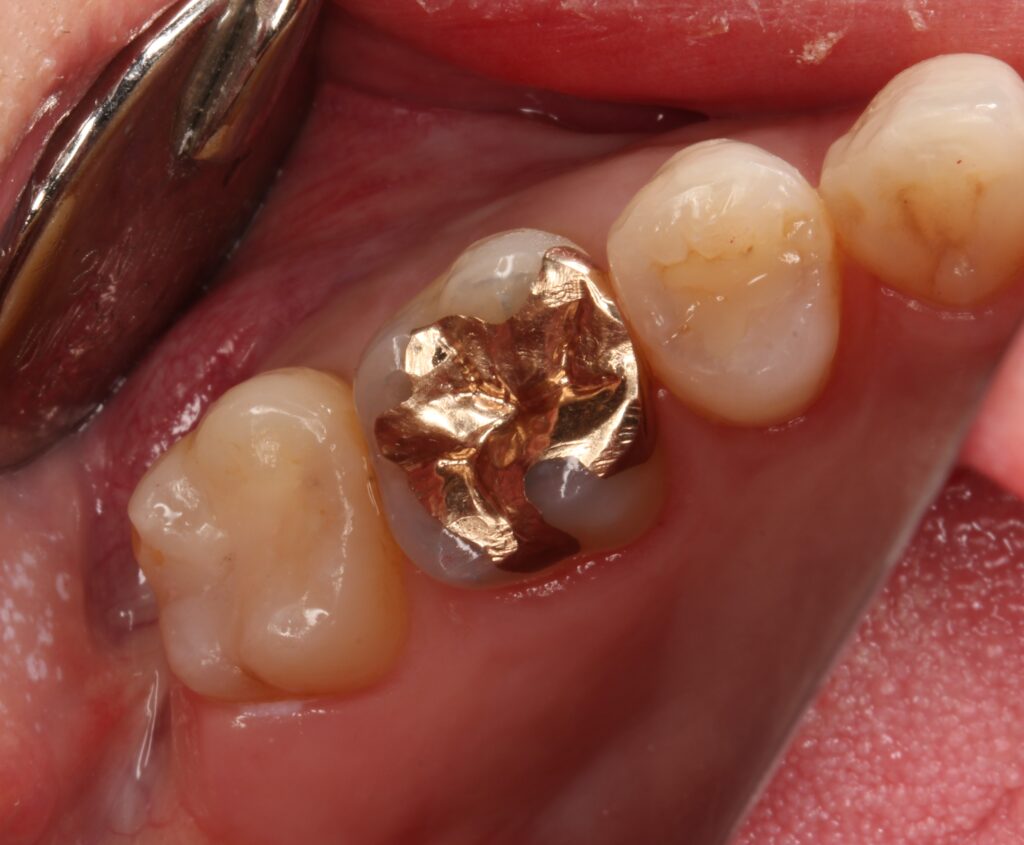

・セラミックインレーがずれて付けられている

先日、セラミックインレーで治療をしてもらうも違和感があるという患者さん。

奥歯の2本の歯にセラミックインレーが入っている。

患者さんは、セラミックが浮いて合っていない感じがすると訴えている。

エックス線写真(レントゲン)で確認してみると、

歯とインレーの間に隙間や、ズレを認める。

担当医でやり直しはしてもらえず、当院で再治療を行う。

こちらは歯科医師の技術力による不具合。